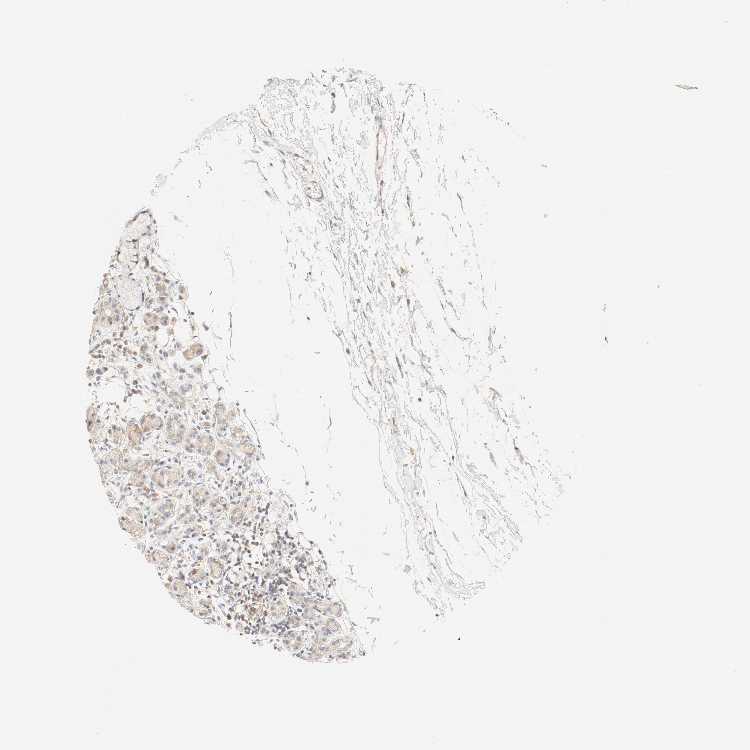

SOFT TISSUE 1 - Antibody stainingi

Antibody staining in the annotated cell types in the current human tissue is reported as not detected, low, medium, or high, based on conventional immunohistochemistry profiling in selected tissues. This score is based on the combination of the staining intensity and fraction of stained cells.

Each image is clickable and will lead to virtual microscopy that enables deeper exploration of all samples and also displays staining intensity scores, fraction scores and subcellular localization as well as patient and tissue information for each sample.

Antibody HPA004059Antibody HPA004186

Chondrocytes -Low

Fibroblasts Not detectedNot detected

Peripheral nerve -Low

SOFT TISSUE 2 - Antibody stainingi

Peripheral nerve -Medium